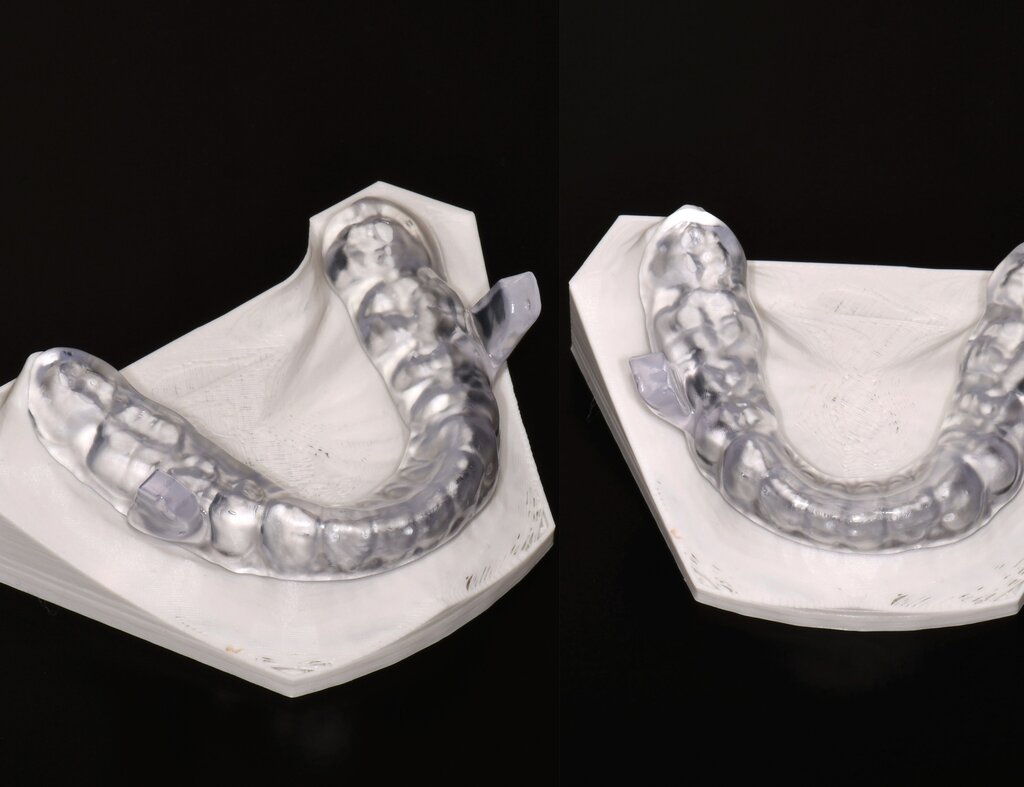

Unter den digital gefertigten kieferorthopädischen Apparaturen sind Aligner wohl das bekannteste Beispiel [Ercoli et al., 2014, Robertson et al., 2020]. Die Herstellung von Alignern selbst basiert(e) jedoch auf einer manuellen Fertigung anhand 3-D-gedruckter Modelle und stellt(e) somit bisher eher eine partiell automatisierte Fertigung dar. Die neuesten Entwicklungen erlauben mittlerweile eine Fertigung im direkten 3-D-Druckverfahren [Tartaglia et al., 2021], so dass mühsame, zeitaufwendige Zwischenschritte der manuellen Fertigung entfallen (Abbildung 1a). Weiter profitieren die Patienten von individuelleren Fertigungsmöglichkeiten, da durch die Umsetzung im 3-D-Druck zusätzliche Elemente einfacher und stabiler in den Aligner inkorporiert werden können (Abbildung 1b).

Als hochinnovatives Feld hat sich auch die Herstellung herausnehmbarer Apparaturen im 3-D-Druck entwickelt (Abbildung 4), beschränkt sich jedoch noch auf einzelne Forschungsansätze [Al Mortadi et al., 2012; van der Meer et al., 2016; Graf et al., 2022; Keller et al., 2022]. Intensiv an neuen Konzepten in der Herstellung 3-D-gedruckter herausnehmbarer Apparaturen wird am Universitätsklinikum Heidelberg geforscht. Da herausnehmbare kieferorthopädische Apparaturen im Regelfall bei jungen Patienten eingesetzt werden, kommt dem Vorteil einer unbegrenzten Replikation und einer kostengünstigen und schnelleren Herstellung ein besonderer Stellenwert zu.

Im Unterschied zu konventionellen Apparaturen bestehen die 3-D-gedruckten Apparaturen vollkommen aus Kunststoff. Eine Einarbeitung metallischer Elemente nach dem 3-D-Druck ist möglich [Al Mortadi et al., 2012; Al Mortadi et al., 2024], erfordert jedoch zusätzlichen Zeitaufwand. Zur Herstellung herausnehmbarer Apparaturen eignen sich konventionelle praxisinterne 3-D-Stereolithografie-Drucker, die in vielen Fällen bereits im regulären Praxisalltag zum Modelldruck verwendet werden. Die verwendeten Kunststoffe sollten dabei eine Klasse-IIa-Zertifizierung aufweisen, so dass ein sicherer langfristiger intraoraler Einsatz der Apparatur gewährleistet ist. Weiter muss die Apparatur nach dem 3-D-Druck gemäß den Herstellerangaben nachprozessiert werden. Im Regelfall beinhaltet dieser Prozess ein Waschen in Isopropylalkohol (IPA) sowie eine Nachhärtung im Lichthärtegerät. Eigens durchgeführte Studien sowie die bisherige klinische Erfahrung bestätigen eine hohe mechanische Stabilität, eine hohe Passgenauigkeit sowie eine breite Akzeptanz der Patienten [Roser et al., 2021; Roser et al., 2023; Segnini et al., 2023]. Des Weiteren wecken die 3-D-gedruckten Apparaturen bei den meist jungen Patienten großes Interesse, was wiederum die Trage-Compliance unterstützt. Durch weitere Entwicklungen im 3-D-Druckbereich wird zukünftig auch ein Farbdruck möglich werden.